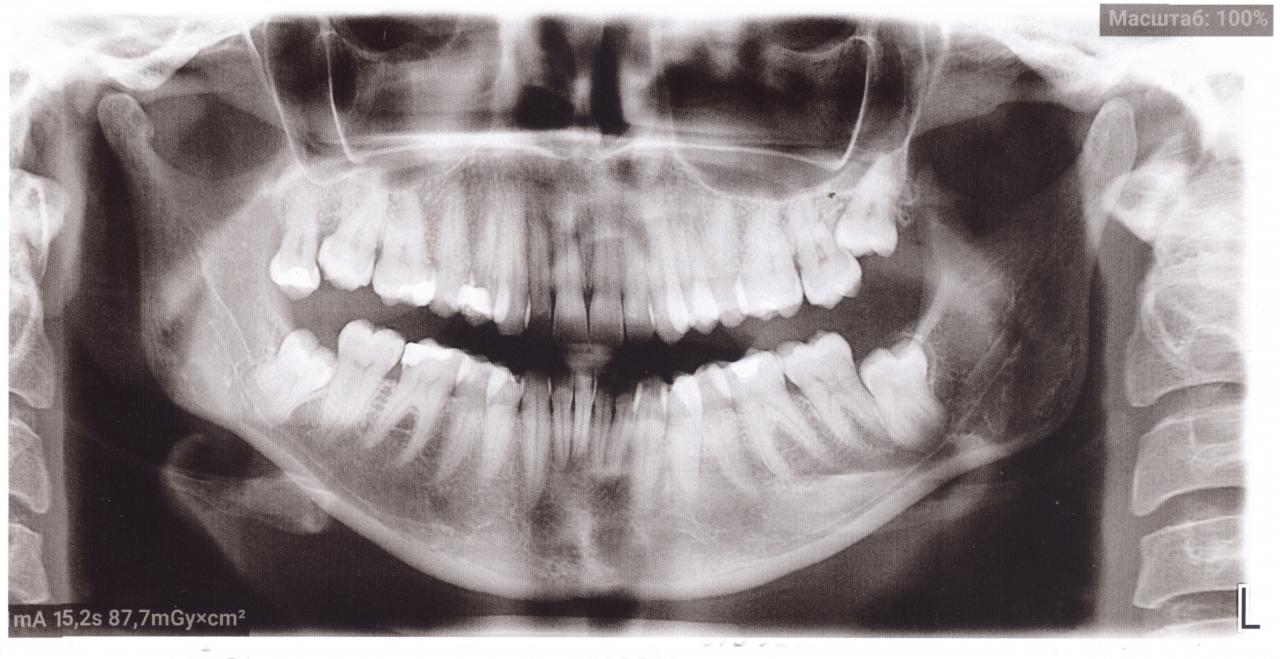

Здравствуйте. Хотелось бы услышать экспертное мнение. Верхние жевательные, с обеих сторон от 4-ок до 6-ок (конкретно сказать не могу), иногда незначительные болевые ощущения, когда ем сладкое. По данному снимку есть проблемы?

Нажмите на изображение для увеличения

Название: панорамный снимок2.jpg

Просмотров: 21

Размер:	101.2 Кб

ID:	13616447

Цитата Сообщение от kvitka_moda Посмотреть сообщение

Вложение 13616447

Если проблемы на щечной поверхности зубов, этот снимок их не покажет.

Электрощетка Орал Би, фторсодержащая зубная паста, уменьшить количество цитрусовых и других кислых фруктов, сладкой газировки и других легких углеводов. Если щетка ручная - чистить от розового к белому.